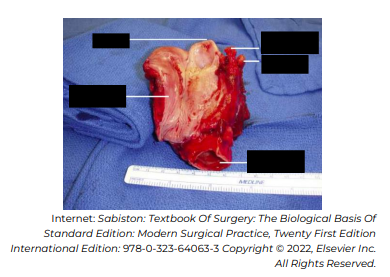

De acordo com a imagem de peça cirúrgica, assinale a alternativa que apresenta o nome do procedimento cirúrgico realizado.